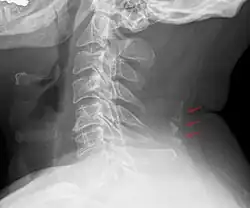

Cou

Les nodules situés dans le bord postérieur du ligament de la nuque forment du tissu osseux chez environ 11 % des hommes et 3 à 5 % des femmes après leur 30 ans et peuvent être considérés comme des os sésamoïdes[14].